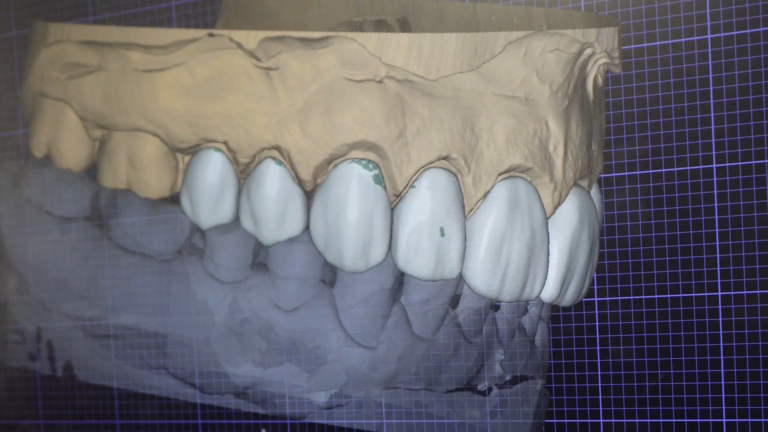

Fațete dentare pentru un zâmbet natural și armonios.